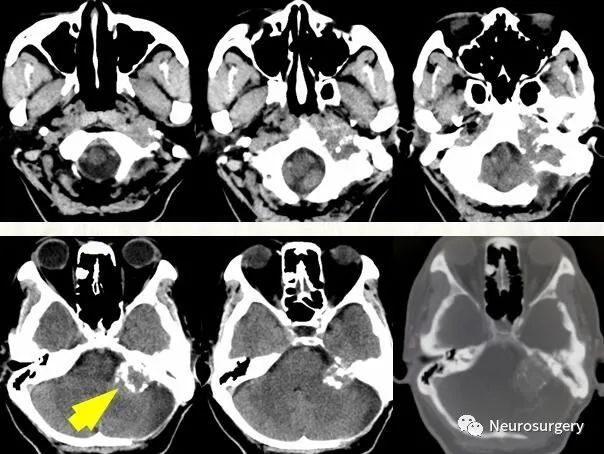

颈静脉球瘤的ct与mr表现病例帖

图片尺寸512x605